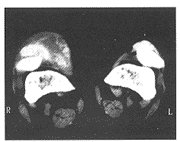

患者男,43岁。入院前10d不慎摔倒致右膝关节着地,3d后右膝关节明显肿胀、积液、剧痛、活动受限,于1996年4月26日来我院就诊。体检:双膝关节肿胀,以右膝关节显著,皮肤紧而发亮,皮温稍高,有剧烈压痛,右膝关节屈曲受限,手、足、肘、膝等部位可触及多处皮下结节。X线片示右髌骨前方有一约7cm×4cm的肿块,内有斑片状高密度影及斑点状钙化,右髌骨表面显像欠佳,关节内髌下脂肪块透亮度正常。B超检查示右髌上囊偏内侧明显膨隆,囊壁厚且不光滑,腔内有少量粘稠液体,满布细小光点,加压可见液体移动,囊壁内无异常血流色彩显示。CT扫描示右髌骨前方巨大软组织肿块,内有斑片状高密度影(图1),肿块边缘部分可见低密度影。左髌骨前方亦见软组织肿块,但较右侧小,关节内积液,髌骨呈缺损性破坏。实验室检查:血尿酸1398.25μmol/L,关节穿刺液检查见尿酸盐结晶。诊断:右膝髌前痛风性尿酸盐结晶沉积。入院后采取卧床、患肢制动,并给予痛风利仙等药物治疗,1个月后右膝关节肿块缩小,皮肤红肿消失,皮温正常,无压痛,膝关节屈伸活动正常,血尿酸降至正常水平。

图1 CT扫描示,右膝关节髌骨前方巨大

软组织肿块,内有斑片状高密度影